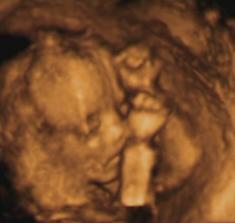

Moj prvy pokladik